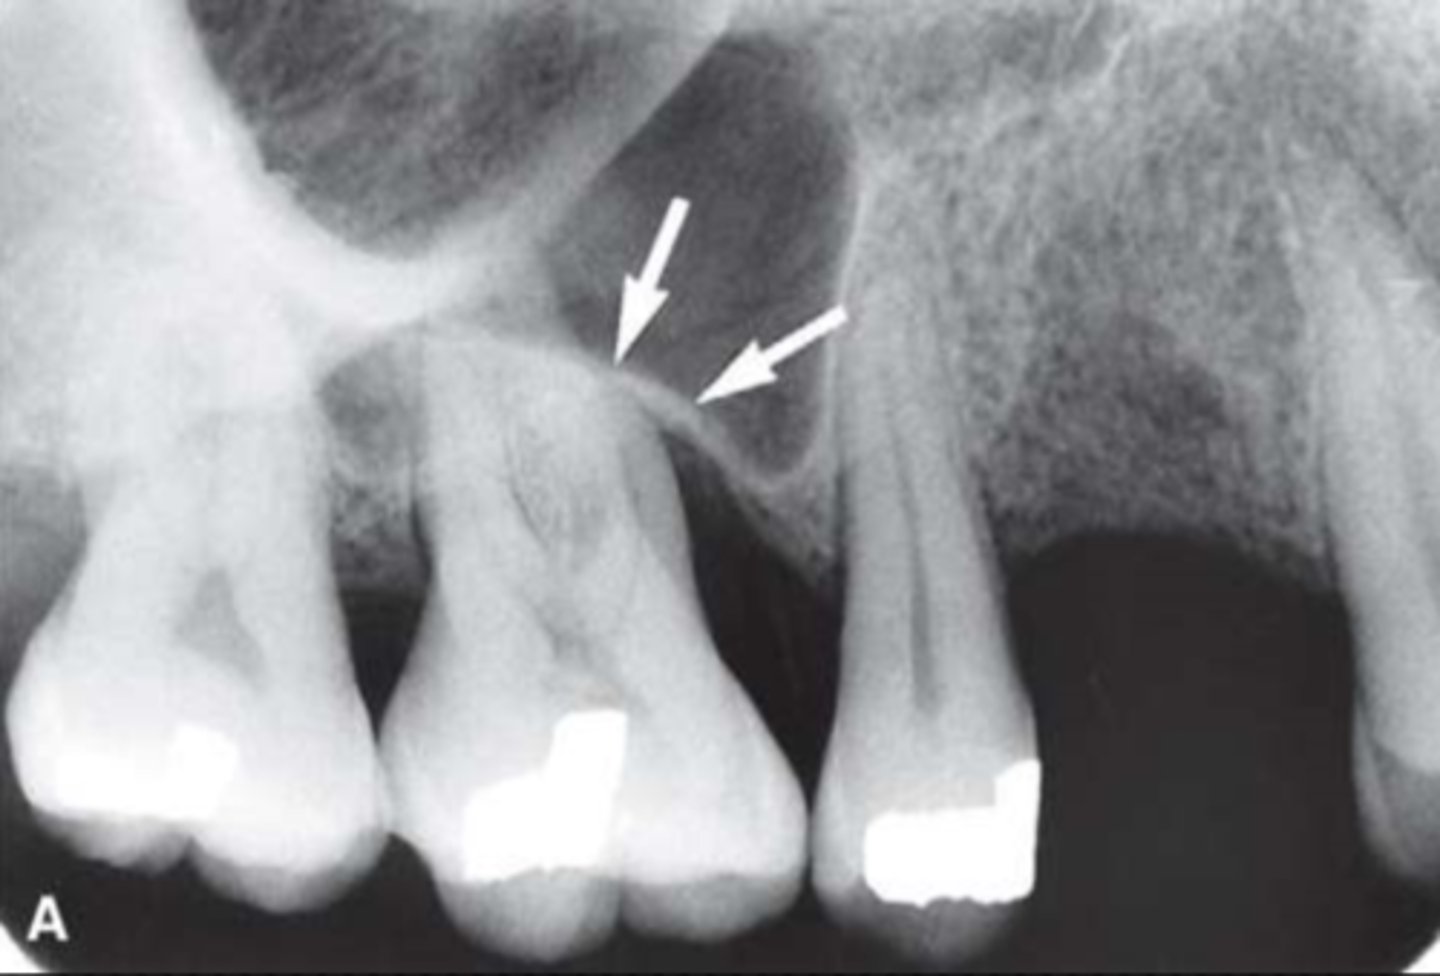

49

New cards

Zygomatic process of the maxilla

Name the curved, radiopaque structure indicated by the arrows.

<p>Name the curved, radiopaque structure indicated by the arrows.</p>